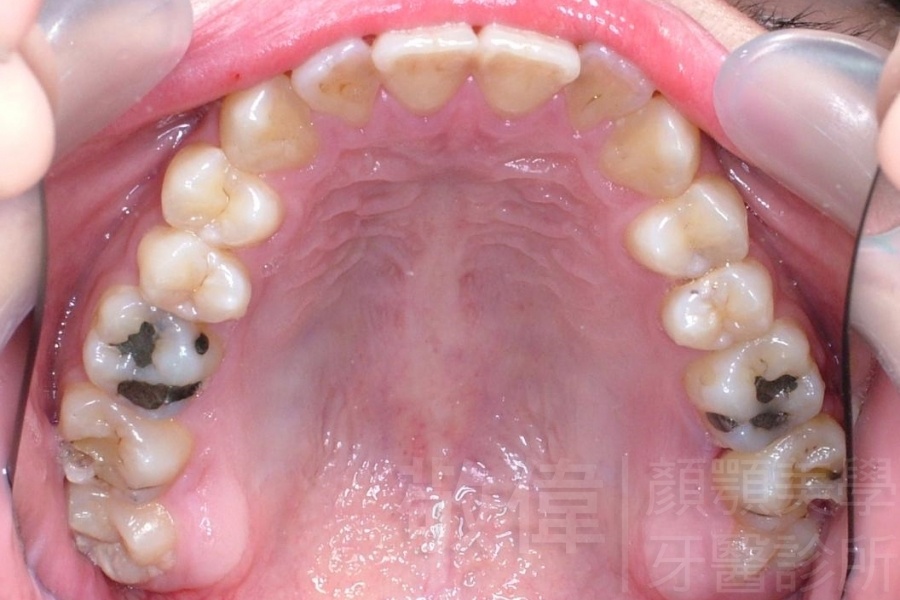

齒顏矯正/上顎暴牙且牙齒極度混亂

矯正前-右   矯正前-正   矯正前-左

矯正前-上   矯正前-下

<個案說明>

上顎暴牙且牙齒極度混亂,經由矯正之後,臉型大幅度改善,牙齒的排列更加的整齊健康。相較於之前眼神充滿精神,自信心展現無遺。